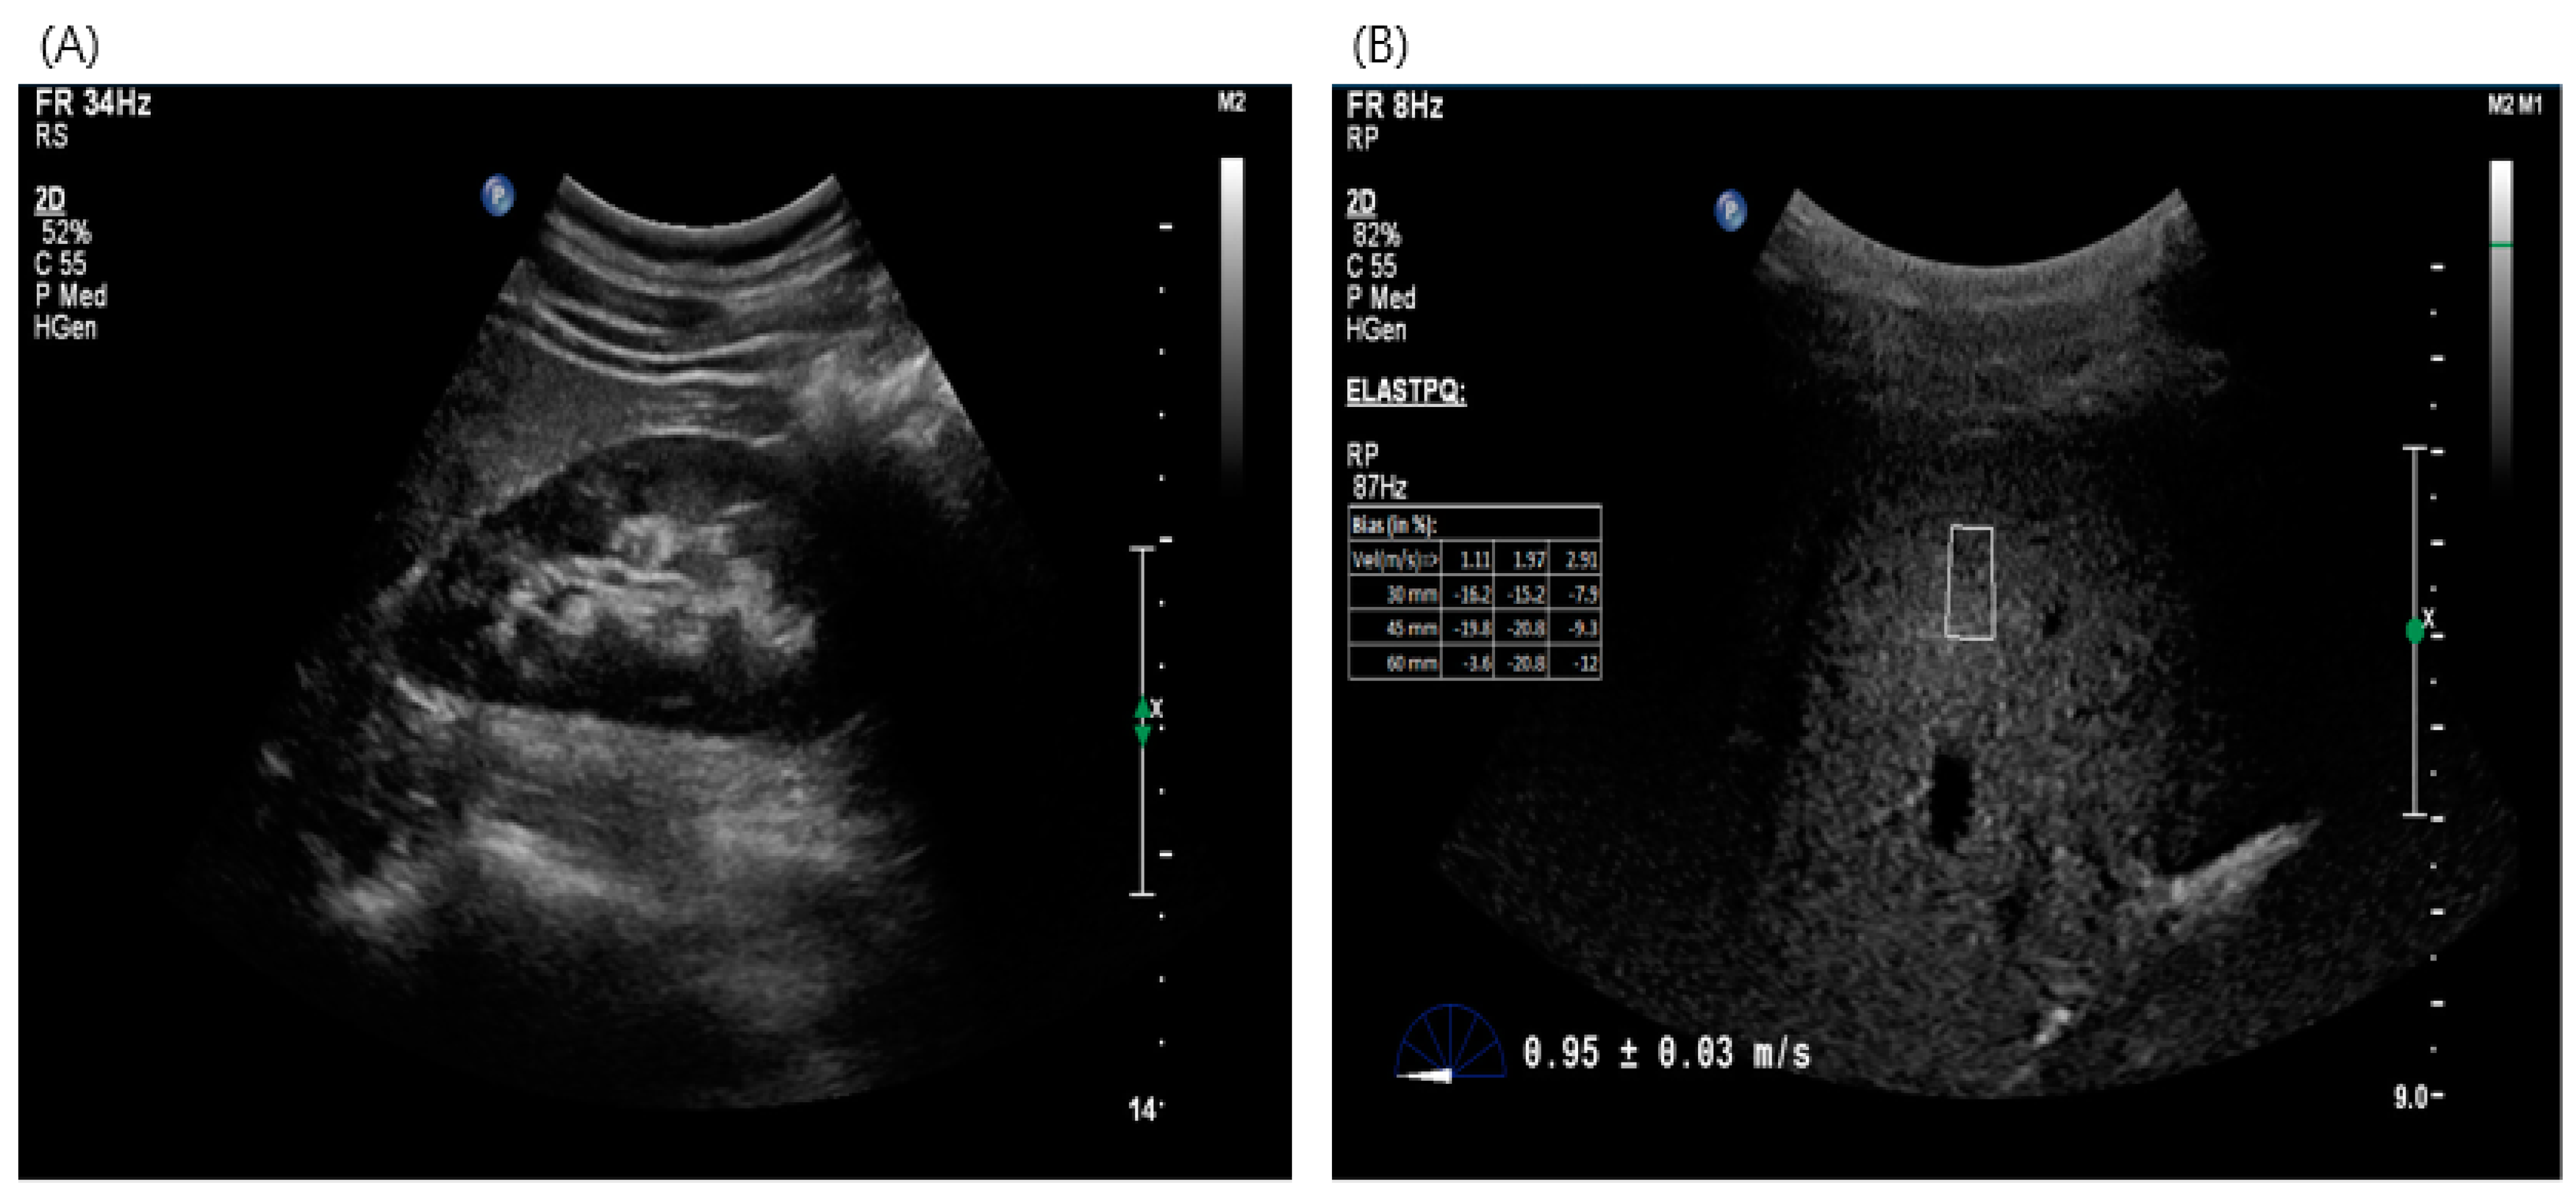

2.3. Imaging Test for Estimation of Liver Fibrosis—Acoustic Radiation Force Impulse (ARFI)